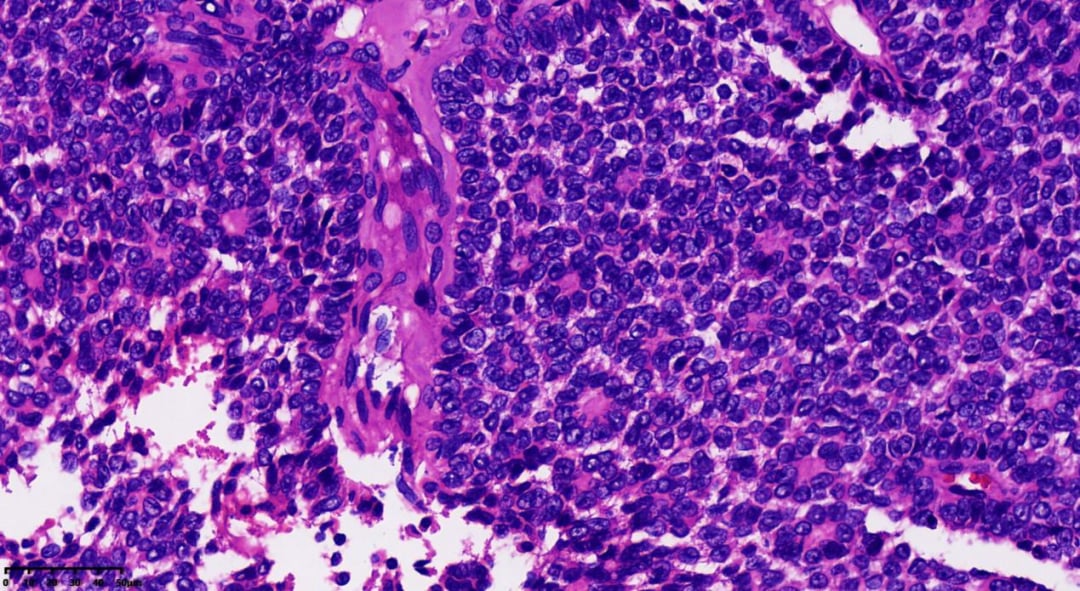

瘤细胞一般胞质稀少,大小较一致,细胞界线不清,卵圆形或多边形,细胞核轮廓不规则,可见核沟或核呈咖啡豆状。核分裂象少见

可见Call-Exner小体

- 组织病理学:瘤组织排列模式多样,同一肿瘤内可能出现多种结构,包括弥漫性、结节状、小梁状、条索样、岛屿状、滤泡状、波浪状、脑回样及肉瘤样。少数病例可见囊性变区域,甚至形成假乳头。瘤细胞通常胞质稀少、淡染,大小相对一致,界线不清,呈卵圆形或多边形,细胞核轮廓不规则,可见核沟或呈咖啡豆状。核分裂象通常较少见,75%的病例中每10个高倍视野(HPF)少于3个。

- Call-Exner小体是AGCT的典型特征,表现为瘤细胞围绕中心腔无定向排列,中心腔内含有核碎屑的嗜酸性分泌物或基底膜样粉染物。

- 部分瘤细胞可能发生黄素化,细胞变大变圆,胞质丰富淡染或嗜酸性,富含脂质,类似黄体细胞,此时核沟不明显,核仁更清晰。